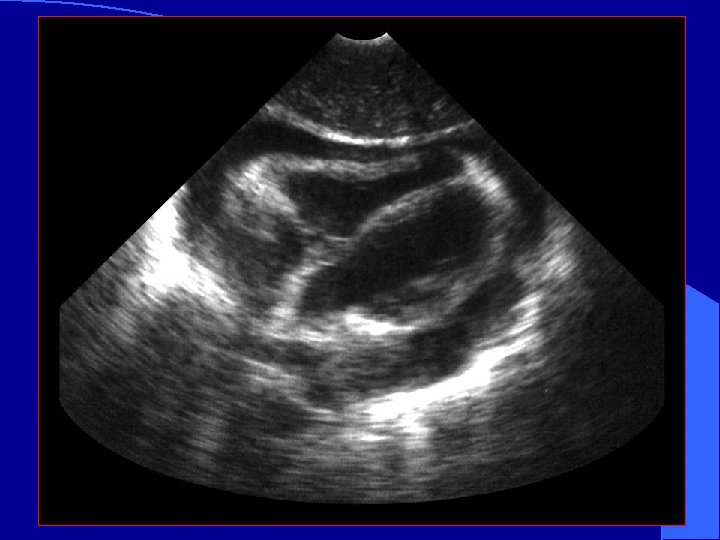

Clinical Case

Clinical Case l Patient is taken to the OR l Penetrating cardiac wound is repaired

Subcostal View l. Most practical in trauma setting l. Away from airway and neck/chest procedures l. Also called Sub- Xyphoid view

Subcostal View

Pericardial Fluid fluid